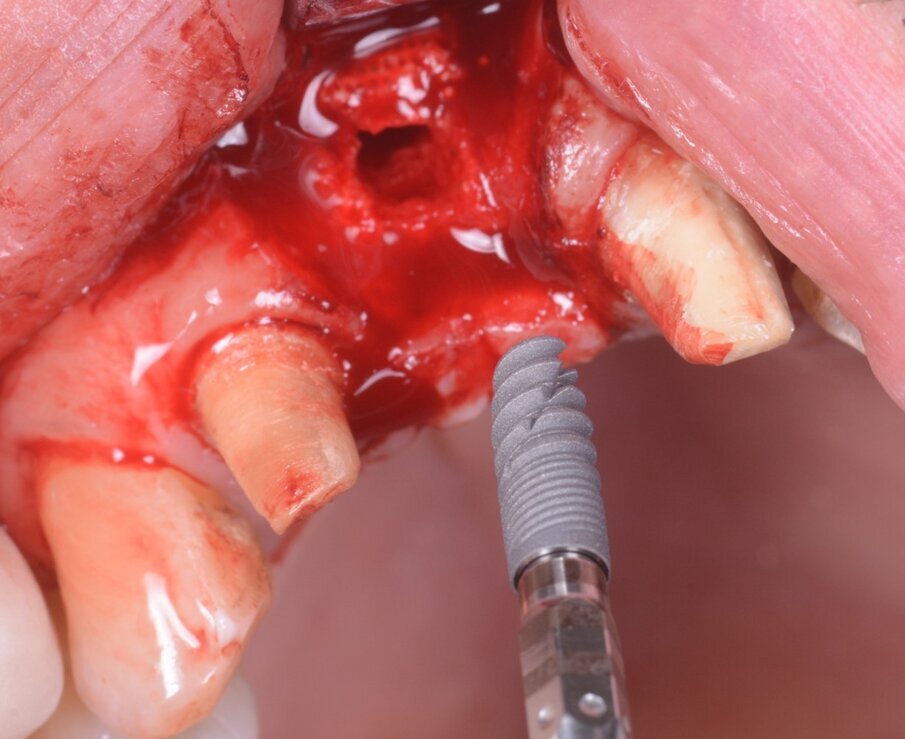

Nel frattempo, le dime chirurgiche erano preparate per la stampa (Fig. 12), stampate con potente stampante 3D stereolitografica (XFAB 3500PD, DWS Systems) e, dopo l’inserimento di boccola fresata in zirconia, pronte all’uso (Fig.13). La preparazione del sito chirurgico avveniva guidata, attraverso l’impiego di 3 mascherine chirurgiche identiche, caratterizzate però da boccole in zirconia con fori dal diametro differente (Figg. 14-17). Tali fori erano specifici per l’uso di ciascuna fresa, perciò non era necessario ricorrere all’uso di riduttori durante la preparazione; e dato che il template chirurgico conteneva già le informazioni relative alla profondità della preparazione, non occorreva impiegare alcuno stop in altezza. Inoltre, non era necessario impiegare frese lunghe, né kits per la chirurgia guidata: l’intervento veniva realizzato utilizzando un kit chirurgico standard, e a lembo aperto. Il posizionamento dell’impianto (Naturactis, Lyra ETK) (Fig. 18) avveniva infine manualmente, per non perdere la percezione della qualità ossea e della stabilità primaria nel sito rigenerato. L’osso recuperato dal sito di fresatura veniva riutilizzato per ulteriore filling vestibolare (Fig. 19).

Fig. 18_L’impianto (Naturactis, Lyra ETK) è pronto per essere inserito manualmente (e non attraverso la dima, in questo caso).